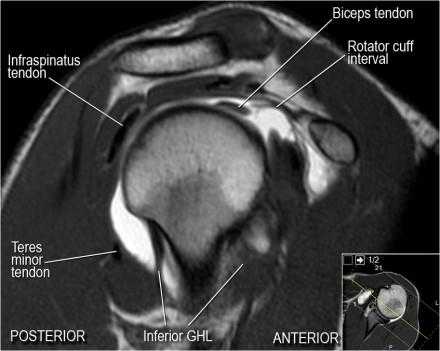

Изображение передних отделов плечевого сустава.

Изображение задних отделов плечевого сустава.